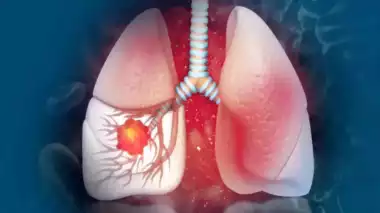

इस तरह के होते हैं लंग कैंसर

इसमें कहा गया है कि एडेनोकार्सिनोमा एक कैंसर है जो बलगम और पाचन में पाए जाने वाले लिक्विड बनाने वाले ग्लैंड में शुरू होता है। और फिर यह धीरे-धीरे लंगों तक पहुंचता है। यह पुरुषों और महिलाओं दोनों को हो सकता है। फेफड़ों का कैंसर कई प्रकार का होता है। 2022 में प्रकाशित एक अध्ययन ने लोगों को चौंका दिया। यह अध्ययन बताता है कि धूम्रपान कभी नहीं करने वाले लोगों में भी लंग्स कैंसर हो सकता है। धूम्रपान नहीं करने वालों में फेफड़ों का कैंसर 53 से 70 प्रतिशत होता था।

धूम्रपान न करने वालों को भी एडेनोकार्सिनोमा कैंसर हो सकता है।

सिगरेट पीने का संबंध फेफड़े के कैंसर (एडेनोकार्सिनोमा) से कम होता है। जैसा कि दुनिया भर में धूम्रपान की आदत कम हो रही है। ऐसे लोग फेफड़े के कैंसर से पीड़ित हैं। जो कभी धूम्रपान नहीं करते हैं फेफड़े के कैंसर के केसेस लगातार बढ़ रहे हैं, क्योंकि धूम्रपान के पैटर्न में बदलाव और हवा के संपर्क में अधिक समय बिताना।

फेफड़े का कैंसर, जो कभी धूम्रपान नहीं करने वाले लोगों में होता है, विश्व भर में कैंसर से संबंधित मृत्यु दर का पांचवां प्रमुख कारण है। जो अधिकांश एशियाई महिलाओं में देखा गया है और लगभग विशेष रूप से एडेनोकार्सिनोमा है।